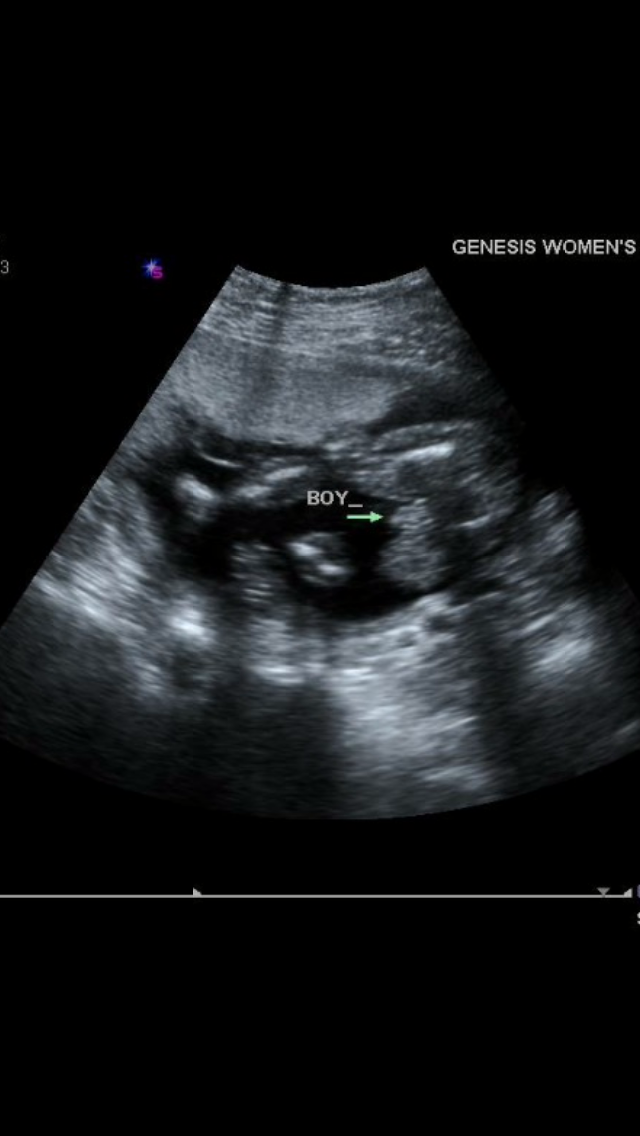

me & my SO found out today we are having a little boy we couldnt be more happy about it, especially because it was what we were both wanting. I'm so happy we get our little boy, but more importantly, we are happy that our little man is healthy & growing! congratulations to all you ladies as well (:

Since the moment I knew and confirmed that I was pregnant I wanted a boy!!!! Then after a month or so I couldn't decide what I wanted as long as my baby was healthy. Two weeks ago I had a 2nd level ultrasound and was secretly praying the gender would be revealed and it would be a boy. PRAYERS ARE ANSWERED....ITS A BOY... KINGSTON LEVI 3/18/16

Found out this morning that we are having a boy! This is both DH and I's first and he has been convinced it was a boy since 12 weeks. I was split down the middle on the wives tales and I was just excited to see him kicking around in there! I had remained mostly in the middle and hadn't "officially decided" what I "wanted". I had my reasoning's for wanting both boy and girl so when the tech showed us, we were not at all surprised or disappointed that he is a little man. Plus, DH is one of two guys left to carry on the family name so I am super excited to bring another boy into the family to help him out!